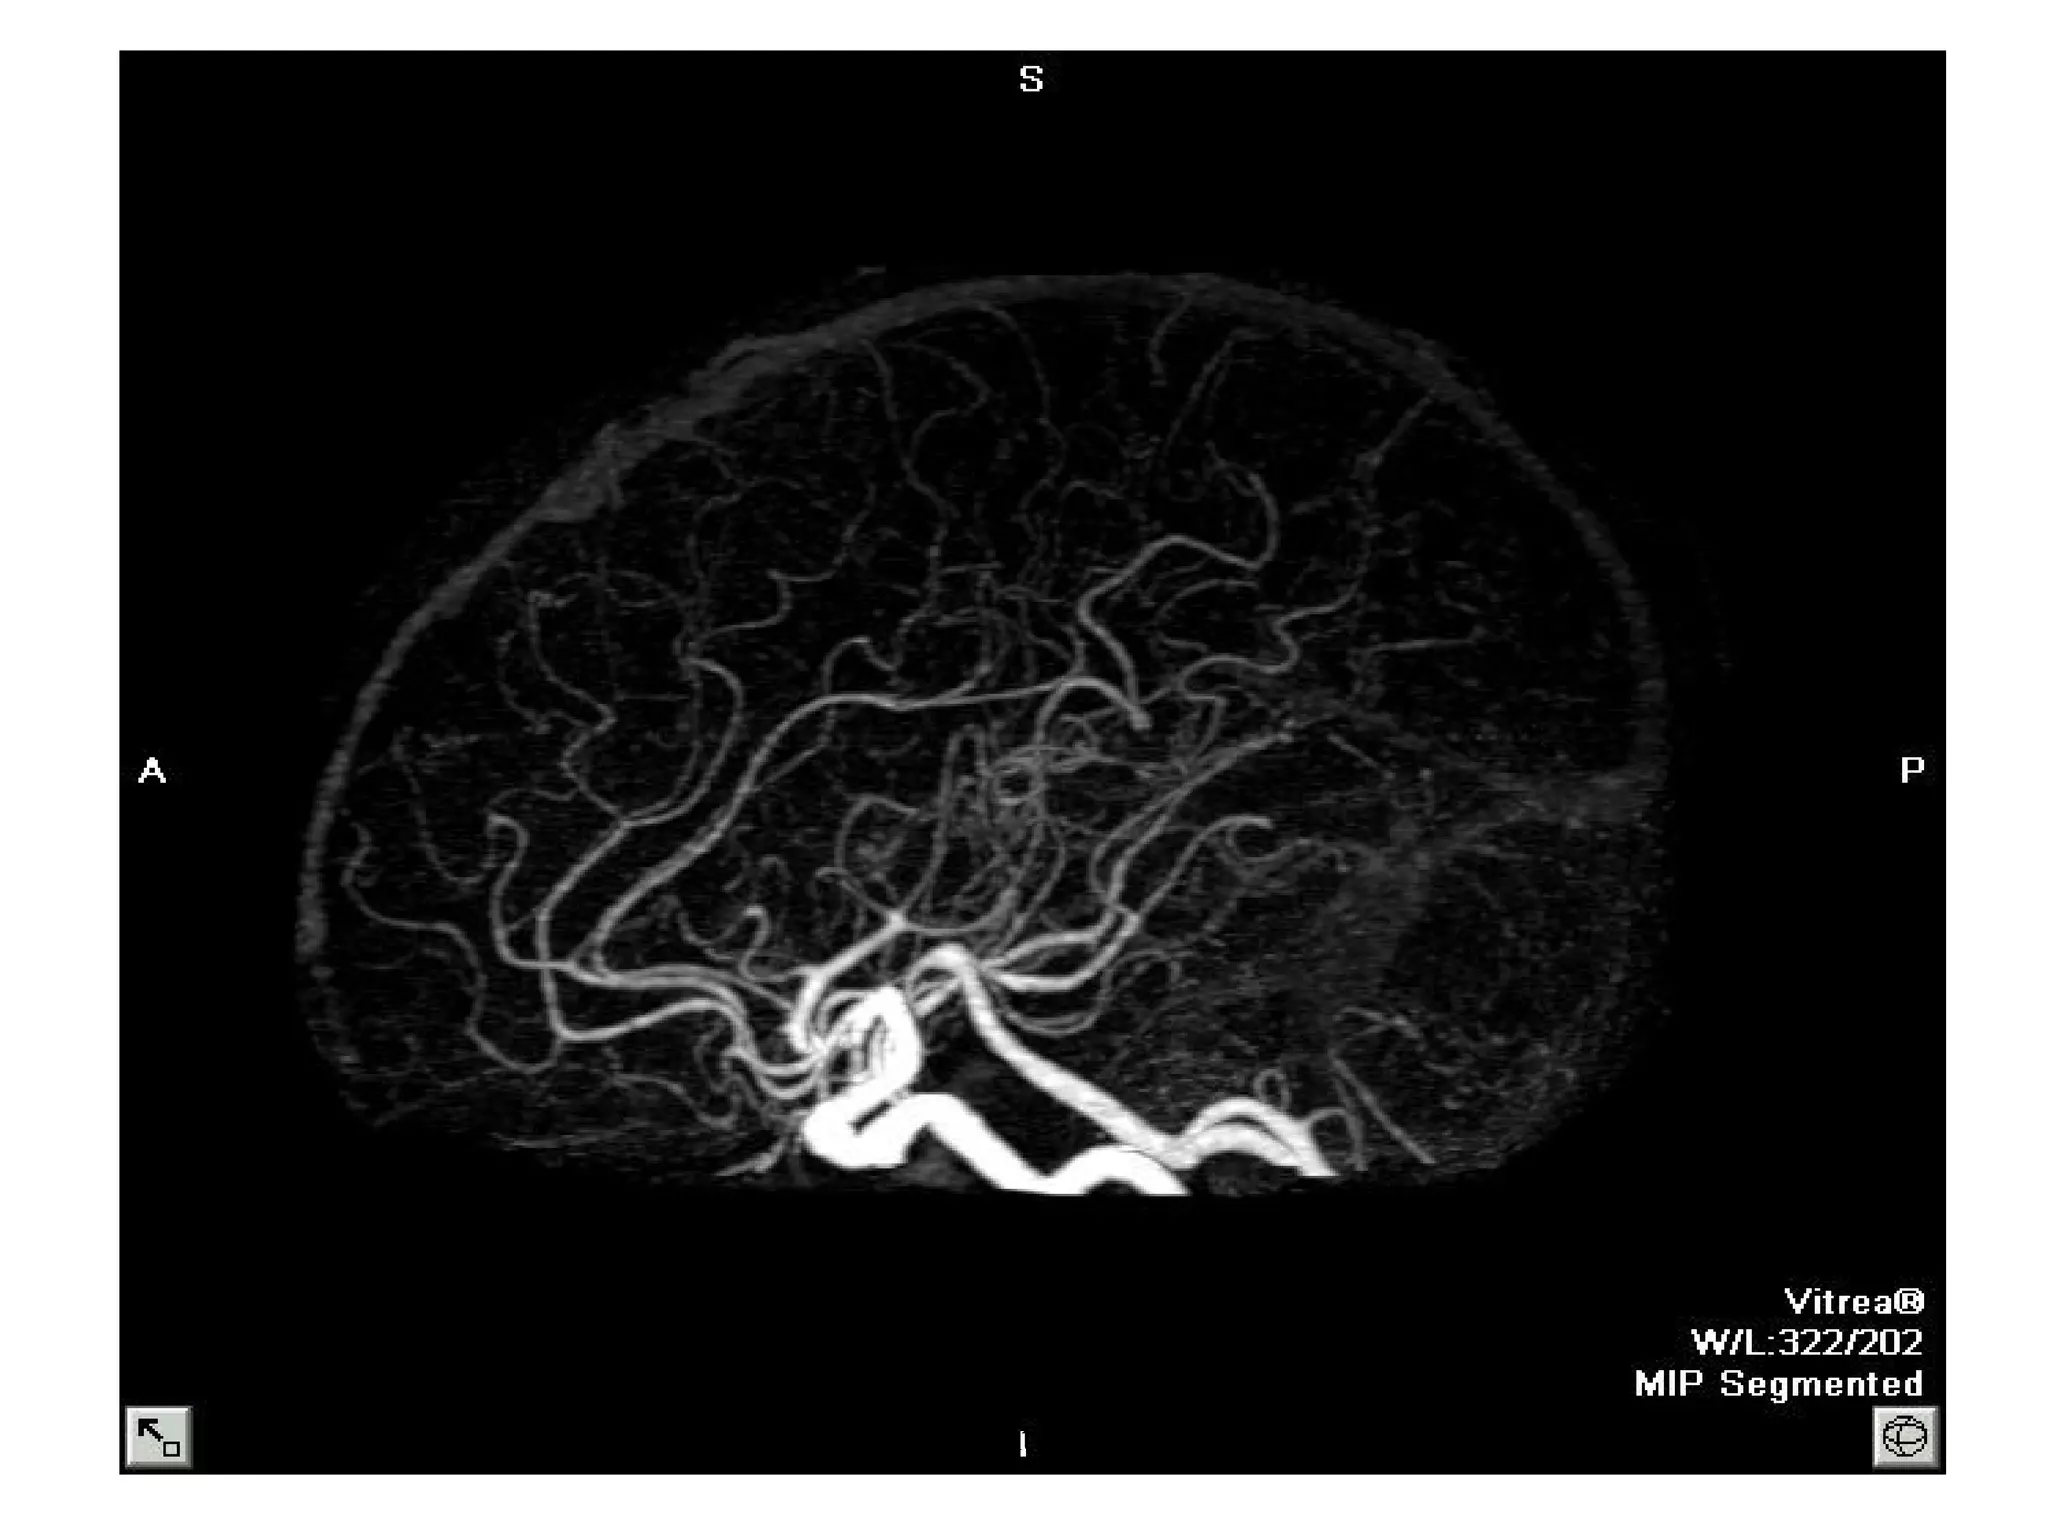

BRAIN ANGIO CTA

SCOUT: LATERAL

LANDMARK: OML

SLICE PLANE: AXIAL

I.V. CONTRAST: 100-140 ML- 3-5 ml /sec -

15 - 20 SEC DELAY CTA

30 SEC DELAY CTV

BREATH HOLD: NONE

SLICE THICKNESS: 1-2 MM

START LOCATION: BELOW SELLAR FLOOR

END LOCATION: 4-5 CM ABOVE SELLA

RECON: 50% OVERLAP

FILMING: 3 D RECON

www.indiandentalacademy.com

DFOV

18